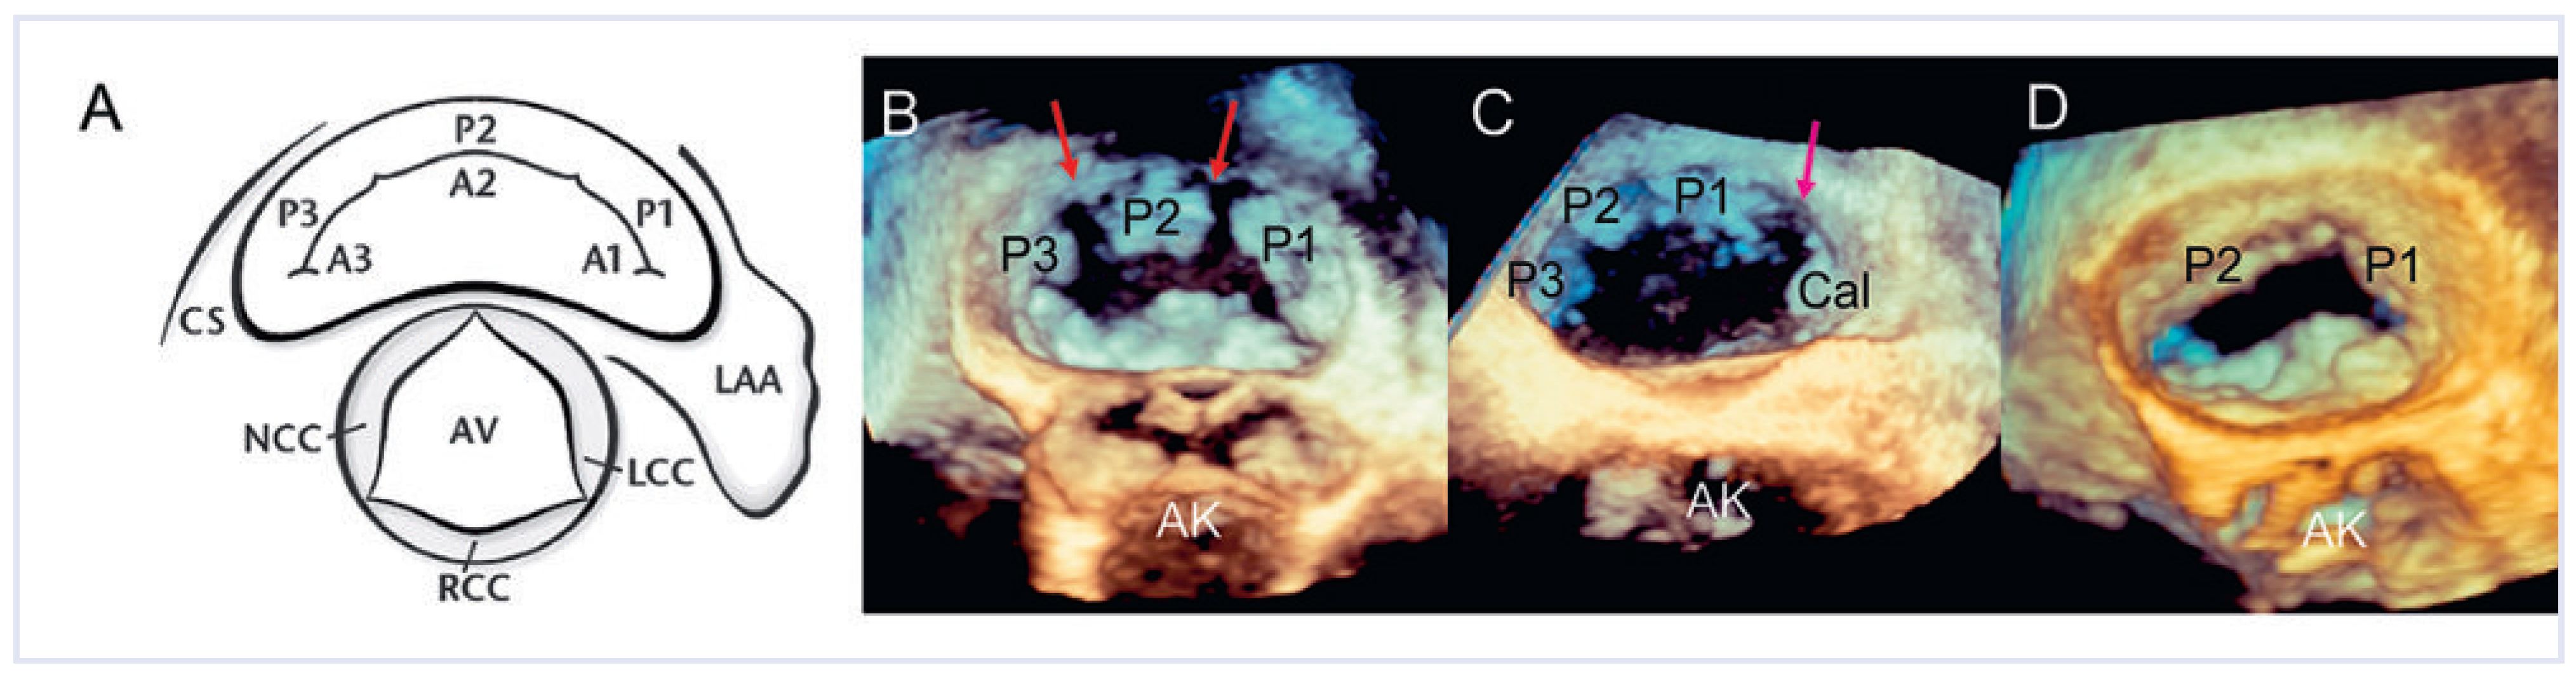

- «xPlane»: die Möglichkeit, gleichzeitig mehrere verschiedene Ebenen zu untersuchen, die in einem vom Untersucher wählbaren Winkel zu einander stehen (Abb. 1A). Zuschalten des Farb-Dopplers möglich (Abb. 1B).

- «3D zoom»: Echtzeit(«live»)-Untersuchung eines pyramidenartigen (dreidimensionalen) Sektors von bis zu 90° × 90° (Abb. 1C). Farb-Doppler nur in der neusten Generation der Geräte möglich.

- «full volume»: Aufnahme eines pyramidenförmigen (dreidimensionalen) Sektors, zusammengesetzt aus 4–7 Untersektoren (keine Echtzeit, Abb. 1D). In der neusten Generation der Geräte Aufnahme in einem Herzschlag. Farb-Doppler möglich (Abb. 1E).